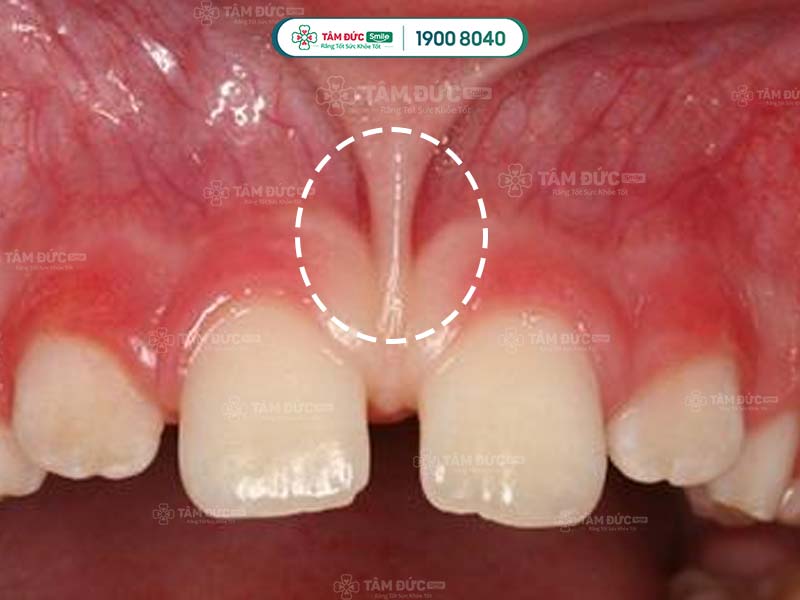

Nằm giữa hàm răng trên và hàm răng dưới là nếp gấp của niêm mạc - nơi tiếp giáp với vùng niêm mạc giữa xương ổ răng và môi. Nếp gấp này khá mỏng và có hình dạng giống lưỡi liềm, thường được gọi là thắng môi. Thắng môi ở phía trên dày và to hơn so với thắng môi ở phía dưới.

Hai bên của răng nanh cũng xuất hiện các nếp gấp tương tự được gọi là thắng bên. Thắng bên ở hàm dưới dày và to hơn so với thắng bên ở hàm trên.

Thắng môi trên